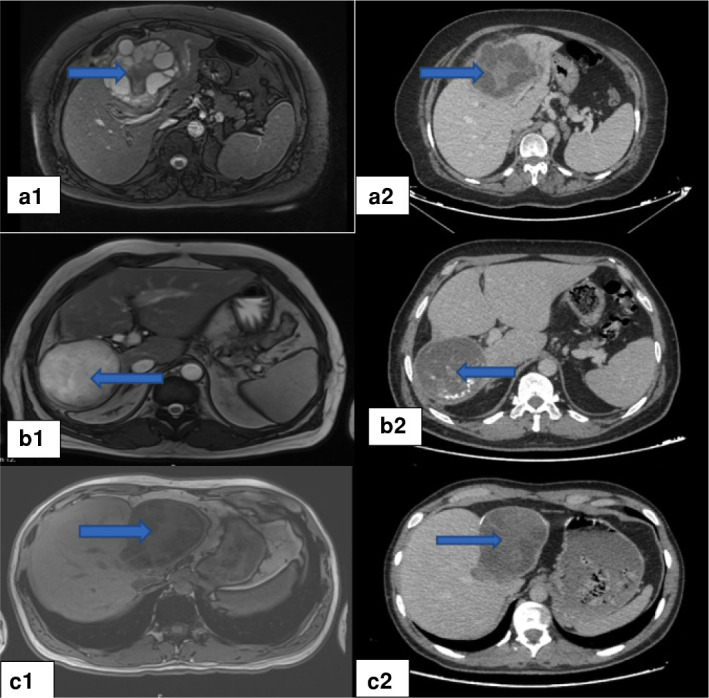

Abstract Image